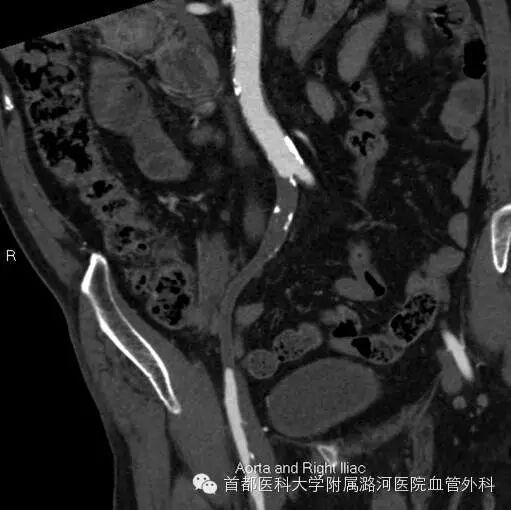

双下肢CTA:

双下肢动脉彩超:考虑右侧髂动脉起始段重度狭窄,余腔内充满低回声。